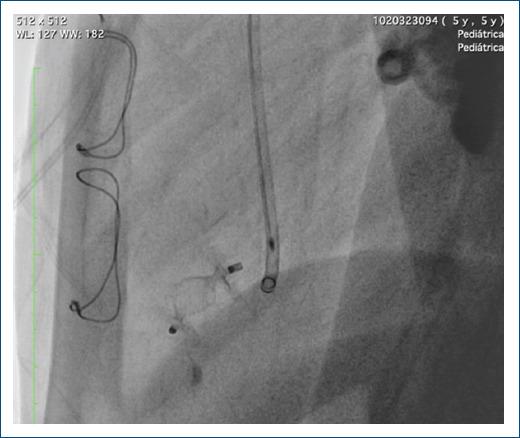

Present other management options for ventricular diverticula, different from surgical options, using alternative materials that are not used very often in daily practice.

A detailed description of a case successfully managed with these new treatment modalities.

Endovascular management of the left ventricular diverticulum, diagnosed prenatally in the patient presented, was successful after initial failure with surgical management.

Endovascular management of ventricular diverticula, using alternative materials to those commonly used, is an attractive option with satisfactory results in these patients.

提出与手术选择不同的心室憩室管理方案,使用日常实践中不常用的替代材料。

详细描述一例成功采用这些新治疗方式的病例。

本文所呈现患者产前诊断出的左心室憩室,在手术治疗初次失败后,血管内治疗取得成功。

使用不同于常用材料的血管内治疗心室憩室,对这些患者而言是一种具有吸引力且效果令人满意的选择。